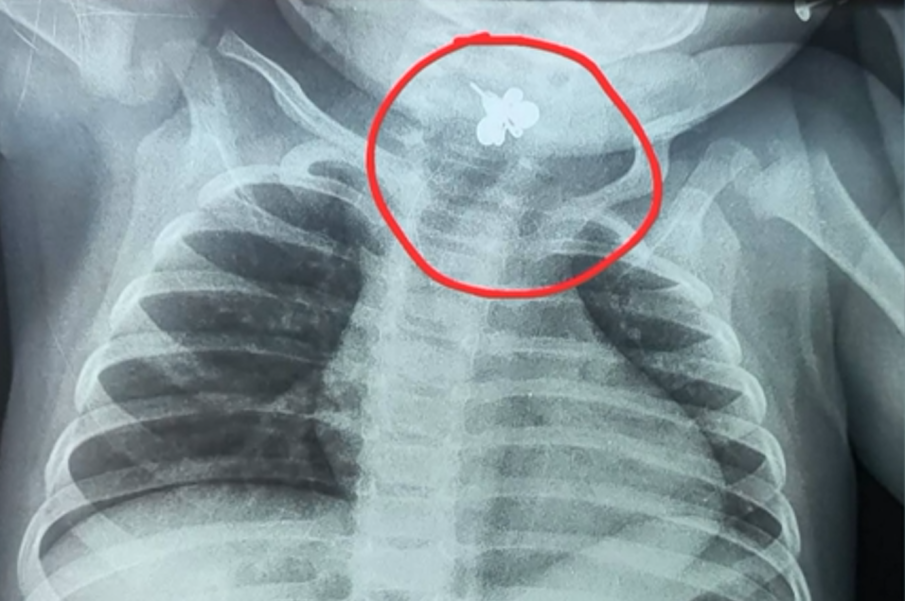

В Парагвай 10-месечно бебе от района на Каакупе е било установено, че е вдишало обеца, след като в продължение на пет дни е имало температура и не е можело да се храни. Първоначално състоянието е било лекувано като инфекция на пикочните пътища, докато рентгенова снимка на гръдния кош не е показала метално чуждо тяло, заседнало в фаринго-ларингеалната област.

Бебето е било транспортирано до Инерам в Асунсион, където лекарите са извършили спешна процедура за изваждане на обицата. Тя е причинила значително възпаление и е довела до затруднено хранене и дихателни проблеми вследствие на бронхоаспирация. Процедурата е преминала успешно, а детето остава интубирано в интензивно отделение под наблюдение, за да се проследи възстановяването му.

"Метален чужд предмет е бил забелязан, заседнал в областта на шията – в цервикалната зона – при това 10-месечно бебе. Родителите бързо се свързаха с нас в Генералната болница и поискахме прехвърляне, тъй като беше изминало твърде много време и това чуждо тяло можеше да причини сериозни последствия. При интервенцията установихме значително възпаление и процедурата беше трудна, защото обецата се е намирала дълго време в областта на ларинкса и фаринкса. Това е пречело на детето да се храни или да приема мляко и то е започнало да развива дихателни проблеми вследствие на бронхоаспирация, тъй като е отделяло много слюнка. Днес можем да говорим с известно облекчение, защото процедурата премина успешно. Бебето все още е интубирано и в интензивно отделение, но вече основно за наблюдение и проследяване на състоянието му", разказва докторът.